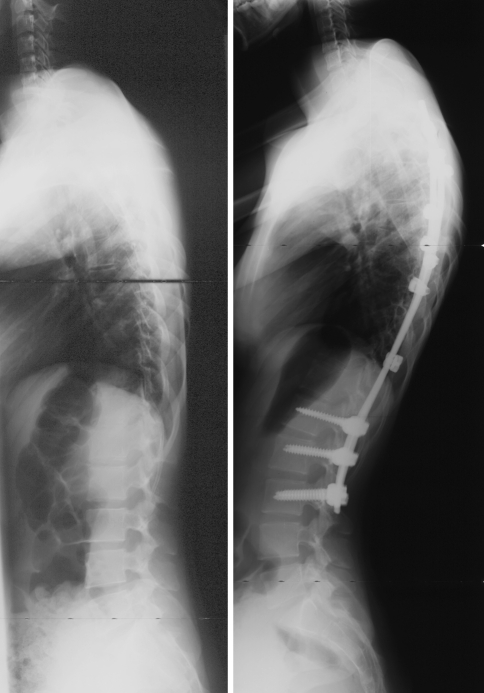

Sagittal plane correction

As shown in Table 4, the mean thoracic kyphosis, which was 23.8° ± 14.2° preoperatively, was 32.3° ± 7.3° at last follow up (P < 0.0001). The changes in thoracic kyphosis according to the preoperative sagittal modifier are detailed in Table 5. For the 68 patients who had a normokyphotic or a hypokyphotic sagittal modifier, thoracic kyphosis increased from 20.5° ± 9.9° to 31.8° ± 7.4°, corresponding to a mean kyphosis correction of 55% at last follow up (Fig. 6). Among the seven patients with a hyperkyphotic sagittal modifier, the mean decrease in thoracic kyphosis was 17.7° ± 9°. Changes between preoperative and last follow-up measurements of lumbar lordosis and T9 sagittal offset are also shown in Table 4. Neither of these parameters was changed significantly.

Fig. 6.

Lateral radiographs, preoperative and at latest follow-up (26 months), of a girl with a Lenke type 1 curve, operated at the age of 16 years. Five sublaminar UCs were used to instrument the main thoracic curve. The thoracic kyphosis was 14° preoperatively, and was improved to 40° after the procedure